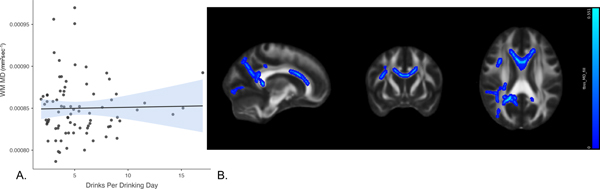

In the model in which WM MD was the criterion and DPDD was the variable of interest, predictors accounted for 21.3% of the variance in diffusivity. Inspection of individual regression slopes indicates that DPDD was positively associated with WM MD, b = .261, t(73) = 2.179, p = 0.033 (note that higher diffusivity suggests WM damage). In the exploratory whole brain analysis, mean diffusivity analyses were conducted in TBSS using DPDD as the predictor, covarying age. Positive associations with MD (Fig 3b) were found in the body and genu of the corpus callosum, superior and anterior corona radiata, and superior longitudinal fasciculus. However, these results did not pass thresholding at p=.05 (see Figure 3).

Figure 3. Association between drinks per drinking day and white matter mean diffusivity.

Panel A shows a scatterplot of the overall association between DPDD and mean diffusivity (in mm2sec−1) in the a priori white matter tracts of interest. Panel B [78, 134, 95] shows the results of exploratory whole brain analyses. DPDD showed positive associations (blue) with mean diffusivity in the body and genu of corpus callosum, superior and anterior corona radiata, and superior longitudinal fasciculus. These images are not thresholded. Significant voxels accentuated for visualization purposes.